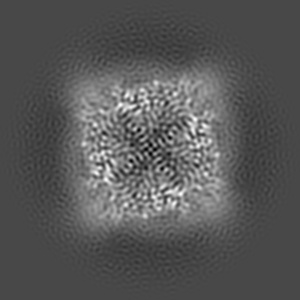

Inactivated-state cryo-EM structure of human TRPV3 in presence of tetrahydrocannabivarin (THCV) in cNW30 nanodiscs

Single-particle3.63 Å

Sample: full-length human TRPV3 in complex with THCV